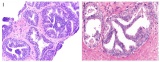

明察秋毫-活检貌似正常的某些肝脏疾病(六)

戈谢病戈谢病(Gaucher disease)是一种常染色体隐性遗传的溶酶体贮积症,可累及肝脏、脾脏、骨髓及中枢神经系统等多个器官。临床表现包括肝脾肿大、骨髓浸润、凝血功能障...